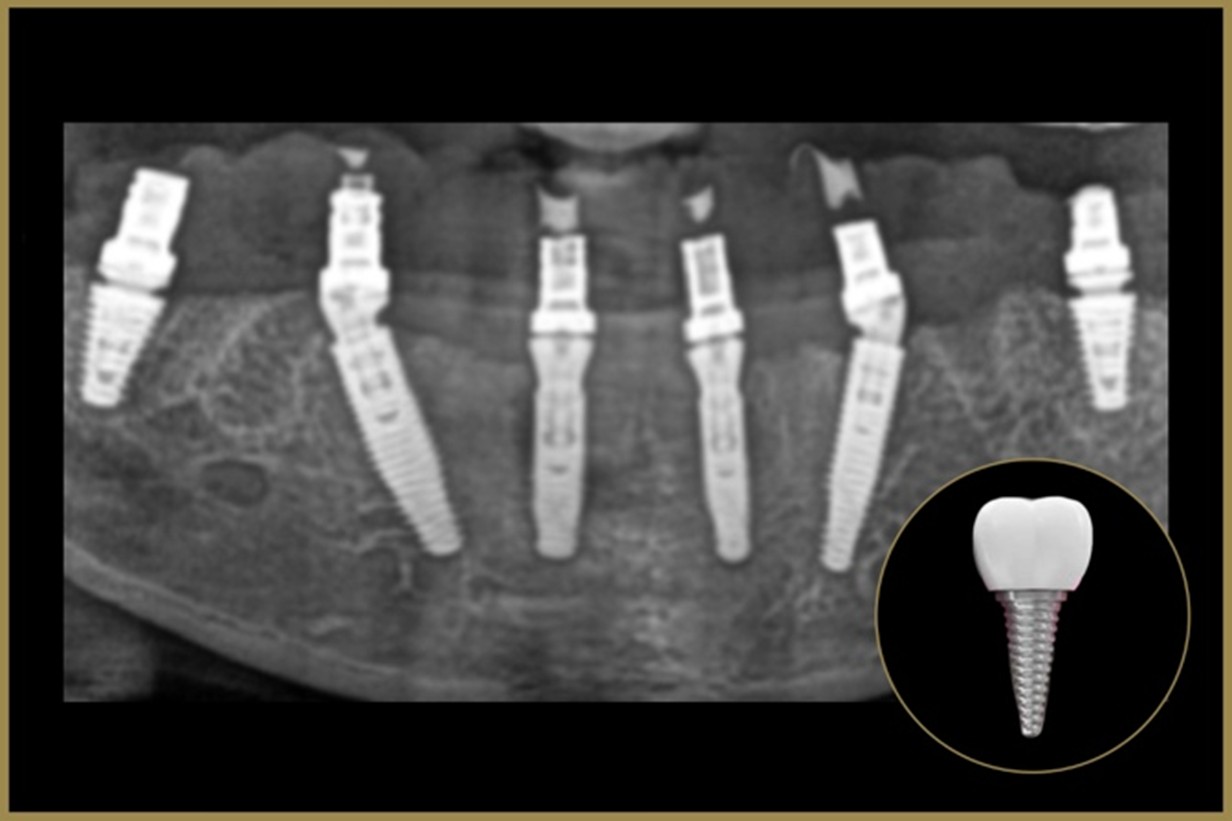

Missing teeth can affect more than just your smile—they impact chewing, speech, confidence, and overall oral health. At Elite Dental Care and Aesthetics, we offer Dental Implants, the most advanced and reliable solution for replacing missing teeth. Implants look, feel, and function just like natural teeth, giving you a strong, lasting, and beautiful smile.

A dental implant is a titanium post surgically placed into the jawbone, acting as an artificial tooth root. Once healed, a crown, bridge, or denture is securely attached, restoring both appearance and function. With proper care, implants can last a lifetime, making them one of the best long-term investments in oral health.

Why Choose Dental Implants?

Permanent replacement for missing teeth

Preserve natural facial structure and prevent bone loss

Function like natural teeth for comfortable chewing and speaking

Do not affect or rely on neighboring teeth

Long-lasting solution with proper oral care

Benefits of Dental Implants

Natural Appearance – Look and feel like your own teeth

Improved Confidence – Smile, eat, and speak without hesitation

Bone Preservation – Prevents jawbone shrinkage after tooth loss

Durability – Designed to last many years, often a lifetime

Enhanced Comfort – No slipping or discomfort like traditional dentures

Whether you are missing one tooth, multiple teeth, or require a full-mouth restoration, implants can be customized to suit your needs. Our team ensures a safe and precise process, using advanced techniques for maximum comfort and predictable results.

At Elite Dental Care and Aesthetics, we restore more than teeth—we restore confidence, functionality, and quality of life with world-class implant solutions.